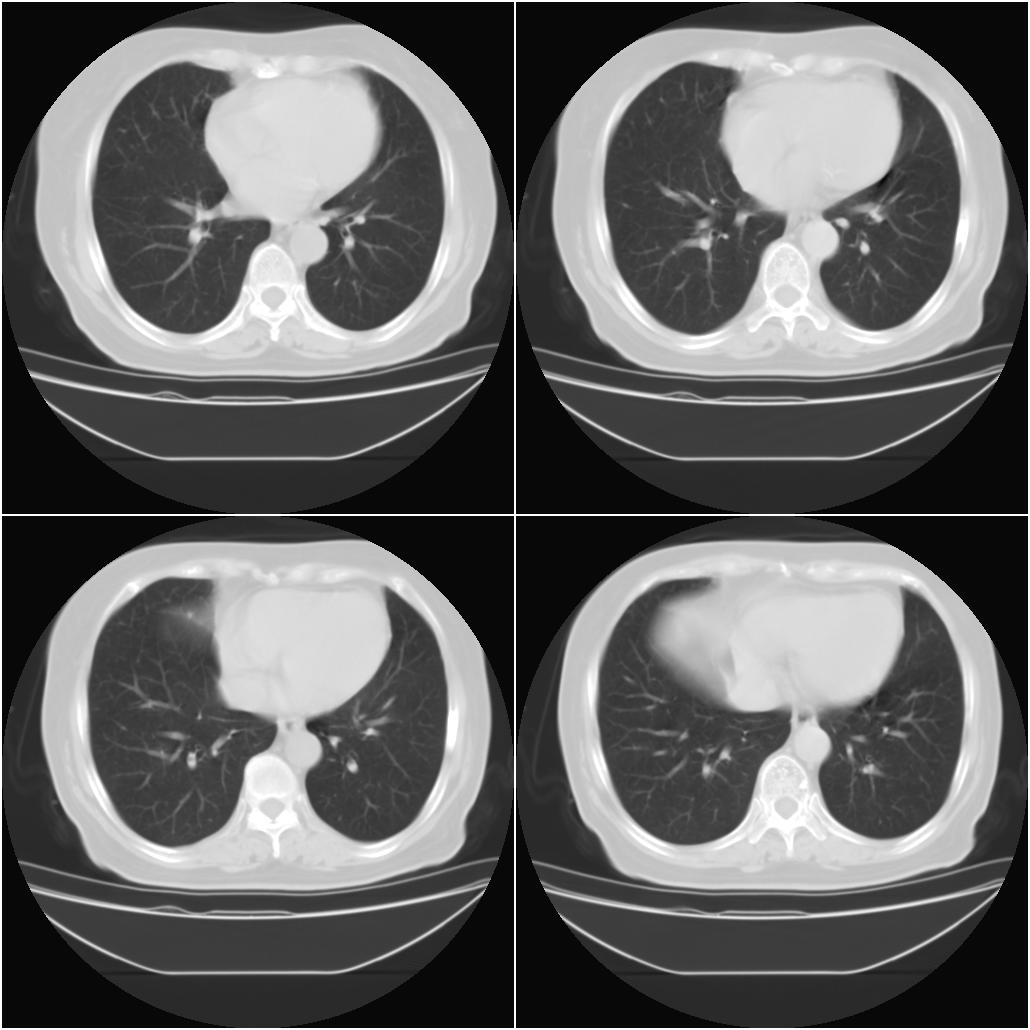

以下是引用sxlcbc在2007-12-23 4:27:00的发言:[br]气管源性肿瘤觉得有点不靠谱啊,看上去气管是受压改变的。更像是上段食管的改变,周围淋巴结肿大,食管受压。看看以下六幅图片:[br]不过,有一点不好理解:食管肿瘤应该有食道症状的,再说食管癌出现周围这么大的淋巴结也不多见啊,如果考虑淋巴瘤倒是更合理一点,这样气管,食管受压改变也许更合理一些。[br][br]